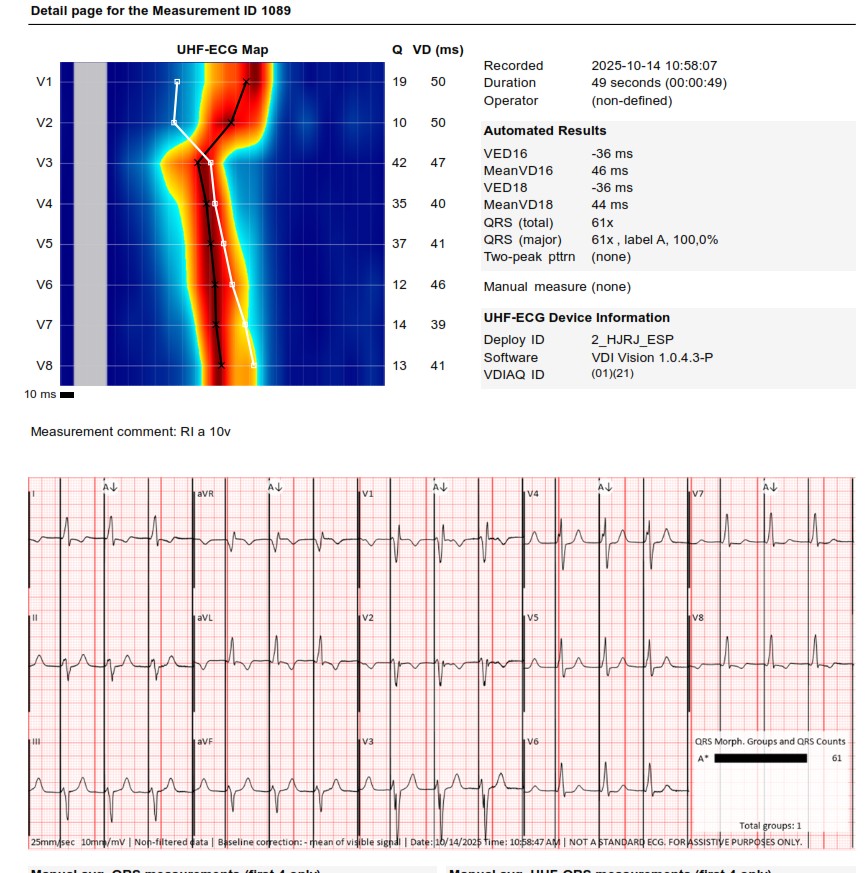

I strongly support HBP, but in this case,the great improvement in QRS didn't correct the asynchrony measured with UHF ECG.We opted for LBBAP despite the RV delay.The final programming AV 70 ms and fusion with native rhythm achieved the best result with UHF ECG(very useful tool)

These are UHF maps of the two patterns. The second one is a little bit deeper into the septum,